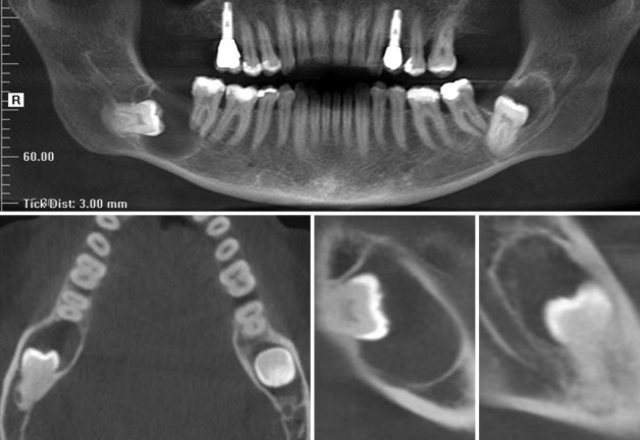

Se comienza de la imagen bidimensional –el radiológico–, o tridimensional. En estos orígenes incluso la interfase de uso de los cuerpos tridimensionales era bidimensional, en base a gráficos que representaban los cortes del objeto, debido a que el universo tridimensional requería de hardware y software de mayor potencia.

Se introduce el Tomógrafo de Haz Cónico

Con los Tomógrafos Computerizados Médicos y luego con los de Haz Cónico, ha evolucionado con enormes ventajas desde sus inicios con DentaScan (1987), 3D/Dental (1988), Siemens MPR/MPD, ToothPix, Allegro-Workstation, Image-Master (1990-1992), SIM/Plant (de Columbia Scientific, 1993), DentalVox, 3D-Doctor, hasta las actuales herramientas muy especializadas para la planificación en cirugía e implantología.